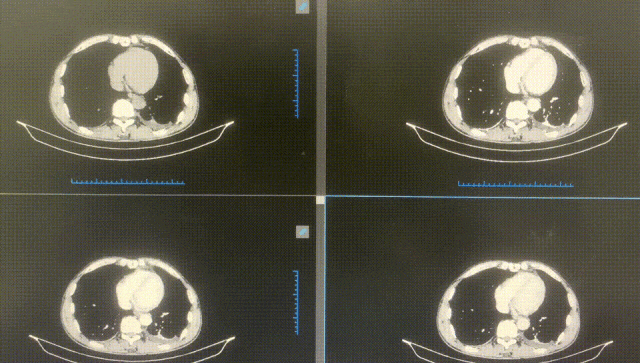

術前